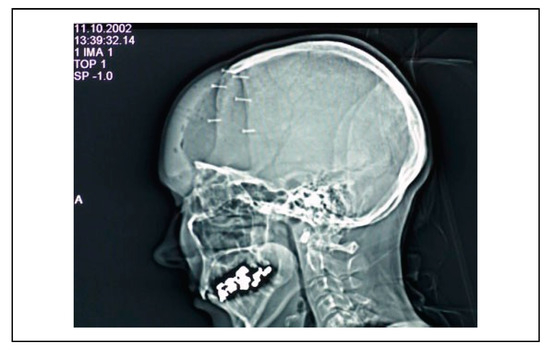

Ceramic 3D-Printed Titanium Cranioplasty

Case Material